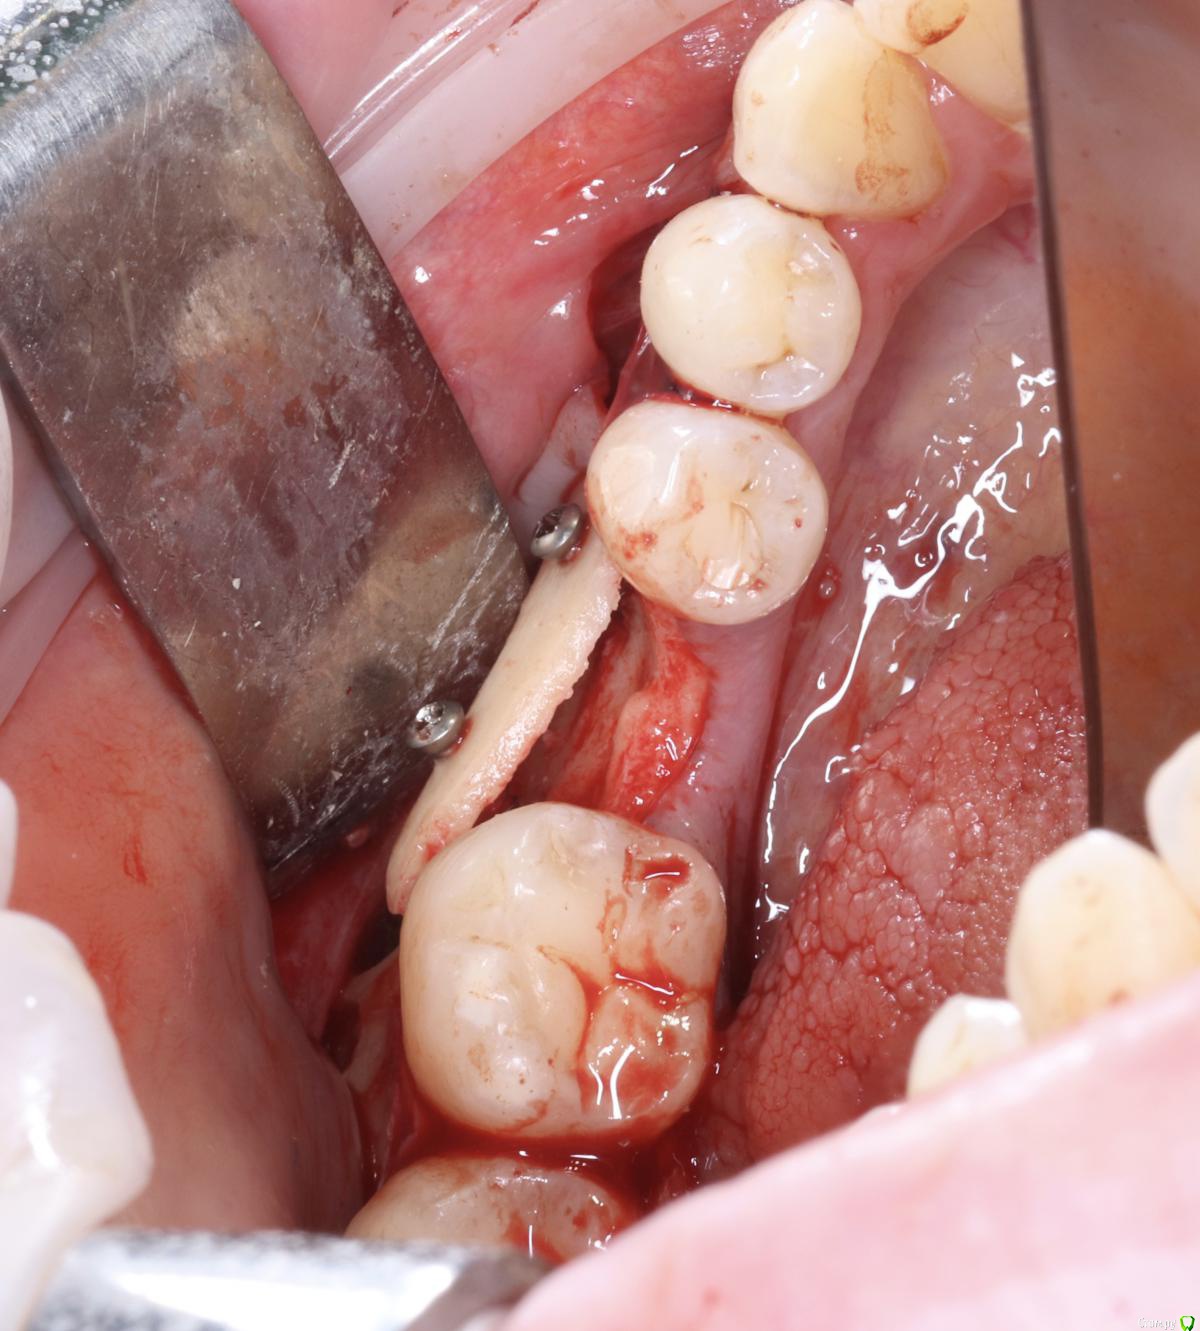

Александр07 Опубликовано 21 августа, 2020 Поделиться Опубликовано 21 августа, 2020 Коллеги добрый день, решил углубиться в тематику костных пластин по Кюри, определенные знания и некоторый опыт есть, небольшой, хотел поделиться последней работой, если какие то советы /замечания есть с удовольствием выслушаю 8 Ссылка на комментарий

Александр07 Опубликовано 22 августа, 2020 Автор Поделиться Опубликовано 22 августа, 2020 толстый очень ламинат. а так все хорошо )Есть смысл перфорировать кортикалку, например как здесь если 1 тип кости ,, как считаете Ссылка на комментарий

АнтонТЛТ Опубликовано 22 августа, 2020 Поделиться Опубликовано 22 августа, 2020 Есть смысл перфорировать кортикалку, например как здесь если 1 тип кости ,, как считаетеАвтор методики считает, что перфорировать вообще нет никакого смысла. 3 Ссылка на комментарий